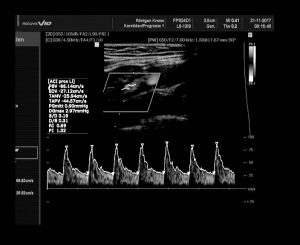

Diese Methode bedient sich des Doppler-Effektes zur Darstellung des Blutflusses, nämlich der Flussrichtung und Geschwindigkeit anhand der Frequenzverschiebung der reflektierten Schallwellen. Duch Messung der Strömungsgeschwindigkeit kann der Stenosegrad eines Gefäßes bestimmt werden.